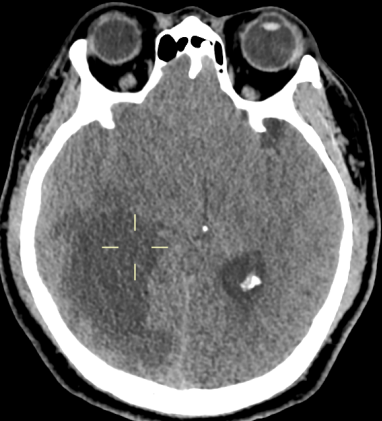

患者中年男性,因“颈部发紧、活动受限伴头晕近半月”入院。PE:NS(-)。头颅MRI平扫+增强检查示右颞枕叶椭圆形囊性肿物,边界清楚,信号均匀,病变周围可见片状水肿,中线结构略向左偏;增强扫描囊壁不规则环状强化(图1)。